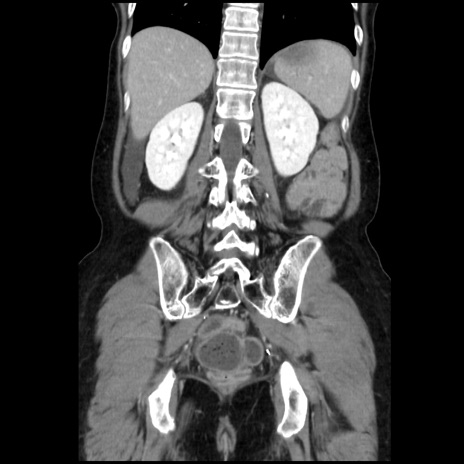

横断像

【症例】40歳代 女性

【主訴】上腹部痛、嘔気・嘔吐

【現病歴】約9時間前頃から急に上腹部痛、嘔気、嘔吐が出現。改善しないため救急要請。

【既往歴】子宮頚癌(広汎子宮全摘術、放射線療法)、腸閉塞

【身体所見】腹部:平坦、軟、腸雑音亢進、上腹部を中心に腹部全体に圧痛あり。

【データ】WBC 8400、CRP 0.03